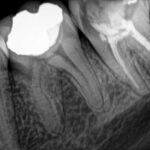

Estas radiografías pertenecen a una paciente que tuvo que realizarse un retratamiento de conducto (es decir que se tuvo que volver a hacer la endodoncia). La paciente presentaba dolor por infección y una pobre obturación con falta de instrumentación de uno de los conductos, (en este molar eran tres y solo se trataron dos y de manera insuficiente). Entonces fue necesario volver a instrumentar (trabajar) los conductos lavando y desinfectando los mismos y por último obturarlos adecuadamente.

La primera radiografía muestra como estaba al venir la paciente y la segunda el trabajo finalizado.

- Aquí puede verse el trabajo deficiente sobre las raíces.